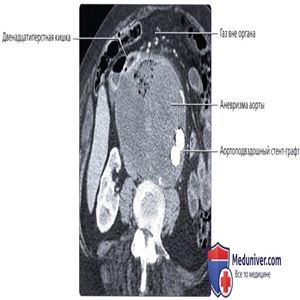

КТ с контрастированием, аксиальный срез: крупная аневризма аорты, оперированная с установкой стент-графта. Обратите внимание, что аорта и прилегающий отдел двенадцатиперстной кишки соприкасаются напрямую без промежуточного слоя жировой ткани. В аневризматической сумке определяется небольшое скопление газа.

КТ с контрастированием, аксиальный срез: у этого же пациента определяется крупное скопление газа в аневризматическом мешке—признак, позволяющий диагностировать аорто-кишечную фистулу. Этот пациент был доставлен в состоянии септического шока и направлен на восстановительную операцию. Даже после оперативного лечения большая часть пациентов с аорто-кишечной фистулой не выживает.

КТ с контрастированием, аксиальный срез: у пациента, ранее перенесшего установку стент-графта, определяется скопление газа в аорте, что характерно для аорто-кишечной фистулы. Первичные аорто-кишечные фистулы встречаются крайне редко, и это состояние почти всегда наблюдается у пациентов, ранее перенесших операцию на аорте.